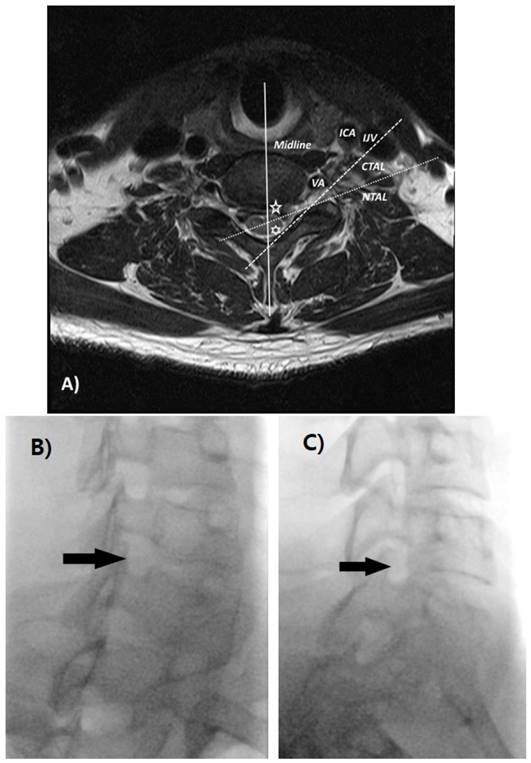

Data were collected by measuring the angles from the axial T2-weighted imaging from C5-6, C6-7, and C7-T1. The axial section image was selected that best observed the inner border of both the foramen and laminar among the intervertebral disc level images at each level. The angles on the axial sections of the MRI imaging were measured using Picture Archiving and Communication System (PACS) software. The first line was drawn from the midpoint of the two articular pillars and passed through the exact midline of the spinous process. In the case of a bifid spinous process, the line was drawn through the midpoint of the bifid process. The second line was drawn parallel to the ventral lamina line (conventional transforaminal approach line, CTAL) [27]. The third line was drawn parallel to the ventral margin at the midpoint of the SAP's ventral border (new transforaminal approach line, NTAL). The angle of intersection between the midline and CTAL, as well as that between the midline and NTAL were measured by PACS software from both sides (right and left) at C5-6, C6-7, and C7-T1 levels. Also, the distance of CTAL and NTAL from VA were measured from both sides at each level. We examined whether the CTAL and NTAL penetrated the ipsilateral VA, internal carotid artery (ICA), and internal jugular vein (IJV; Fig. 1).

A) The midline (solid line, blue) was drawn from the midpoint of the two articular pillars and to pass through the midline of the spinous process. The CTAL (dashed line, yellow) was drawn parallel to the ventral lamina line, and the NTAL (dotted line, white) was drawn parallel to the ventral margin of the superior articular process (SAP). A five-pointed star (green) represents the angle between the midline and NTAL, and the six-pointed star (green) represents the angle between the midline and CTAL. Different fluoroscopic views in a single subject that were taken as part of study; B) oblique 50° C) oblique 70°. CTAL = conventional transforaminal approach line; NTAL = new transforaminal approach line; VA = vertebral artery; ICA = internal carotid artery; IJV = internal jugular vein.